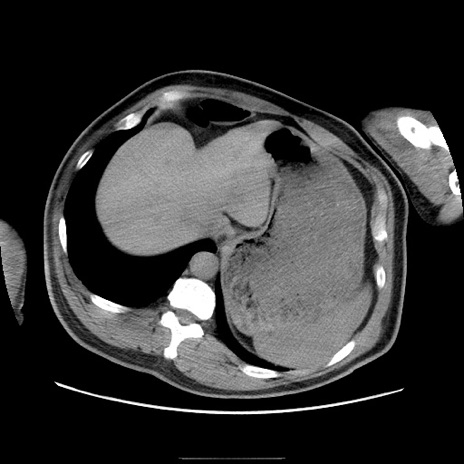

症例

冠状断像